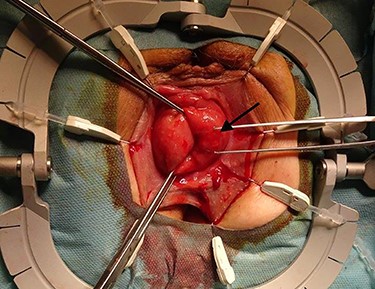

The surgical site was adjusted using a Lonestar retractor and the prolapse was exposed further using Allis clamps (Fig. 2). A monopolar current incision was made slightly above the dentate line, followed by circular dissection of the rectum starting from the ventral aspect (Fig. 3). The entire tumor area between three and six in lithotomy position (3 cm in diameter) was completely reduced (Fig. 4). No penetration was visible on the serosa side. The prolapse was then shortened and a tension-free coloanal anastomosis was created using several Monocryl 4.0 sutures.

Adjusted surgical site using a Lonestar retractor. The rectal prolapse is exposed using Allis clamps. The tumor appears between three and six in lithotomy position (long arrow).